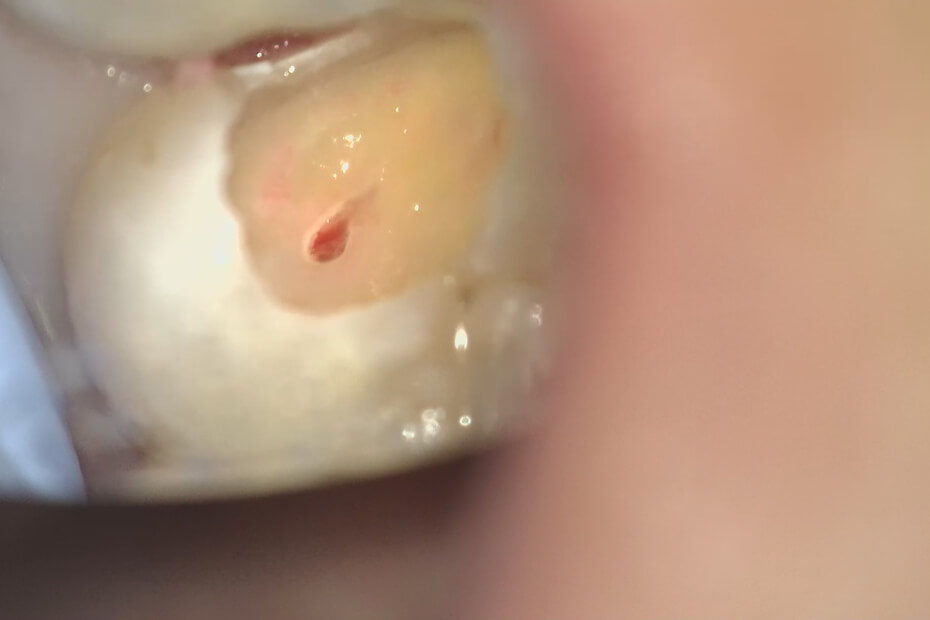

虫歯を除去すると神経が露出したが、顕微鏡で出血時間や毛細血管の構造を確認することができたので、神経は温存できると判断した。

神経を保護するMTAセメントを使用した。